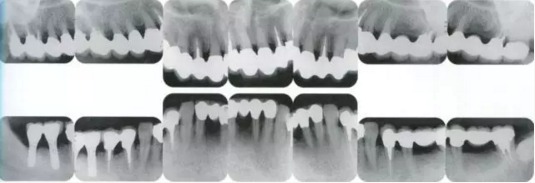

2222222222.png

40歲,女性。來院主訴為牙齦出血,牙體晃動(dòng)。患者不吸煙,因此沒有全身性問題。有明顯的牙周炎,發(fā)生了牙體移動(dòng),前牙區(qū)前突。下頜右側(cè)磨牙缺失,醫(yī)生認(rèn)為有必要進(jìn)行包括牙周修復(fù)、正畸治療、種植治療等在內(nèi)的綜合性治療。

22222222222222.png

▲圖19-2,3

上下頜咬合面照。

22222222222222222222222222.png

▲圖19-4

X光片。牙槽骨明顯缺失。